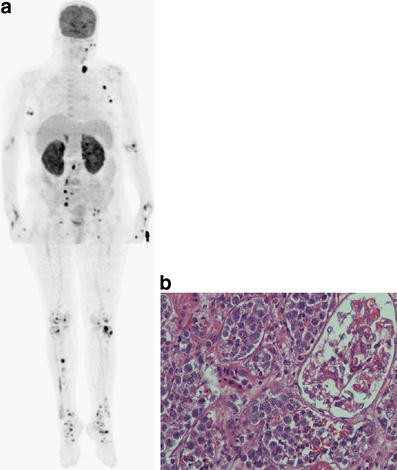

Herein, we report a case of a 61-year-old woman with IVLBCL who presented with fever and weakness. Her routine laboratory findings were uneventful except elevated serum lactate dehydrogenase (LDH) levels and sedimentation values. Imaging studies such as abdominal ultrasonography, chest and abdominal CT and echocardiography studies revealed neither evidence of tumoural lesions nor the origin of fever. Subsequently, 18F-fluorodeoxyglucose (FDG) positron emission tomography (PET) demonstrated an increased FDG uptake in multiple organs such as bilateral kidneys and adrenal glands, uterus, supra- and infradiaphragmatic lymph nodes, and multiple sites of bone marrow. The diagnosis of IVLBCL was established with kidney biopsy performed due to bilateral diffuse intense uptake of renal cortex. Histopathological examination of the renal biopsy demonstrated large atypical lymphoid cells occupying the intravascular space on haematoxylin and eosin staining.

Based on the findings of the present case, we believe PET/CT may be used for detecting locations that are involved with IVLBCL. Moreover, as mentioned in the literature, FDG PET may also have a role in monitoring response to chemotherapy.